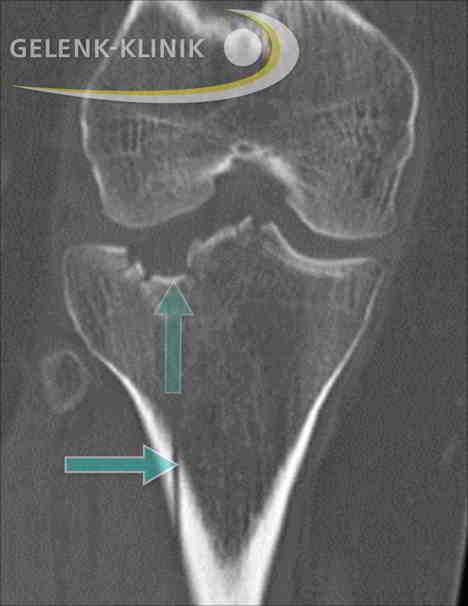

- Die Computertomographie kombiniert Röntgenstrahlen aus verschiedenen Richtungen, um Schnittbilder anzufertigen. Der Zustand des Knochens wird auf diese Weise dreidimensional dargestellt. Brüche des Knochens zeigt das CT-Bild in ihrem gesamten Verlaufs.